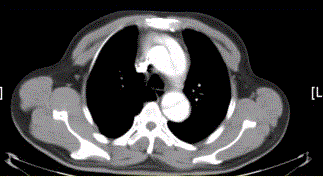

问题 患者男,67岁,高血压病史多年,自服降压药,突发胸骨后剧烈疼痛2h,服用硝酸甘油不缓解。胸透示主动脉增宽。CT影像如下图。 关于内膜瓣,描述正确的是

选项 A.平扫就很容易发现 B.内膜瓣可发现钙化 C.厚度通常大于主动脉壁厚度 D.增强时明显强化故不易显示 E.截面大多呈S型 F.由动脉内膜组成

答案 D

解析 D